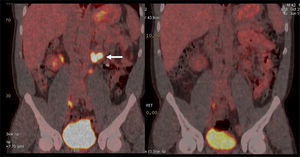

La vigilancia post tratamiento de un CCR suele ser prolongada, ya que las metástasis pueden aparecer varios años después de la cirugía (8). El PET/CT tiene especial valor en la detección precoz de dichas lesiones, permitiendo muchas veces plantear la opción de tratamiento quirúrgico curativo en algunos casos de oligometástasis (Figura 2).